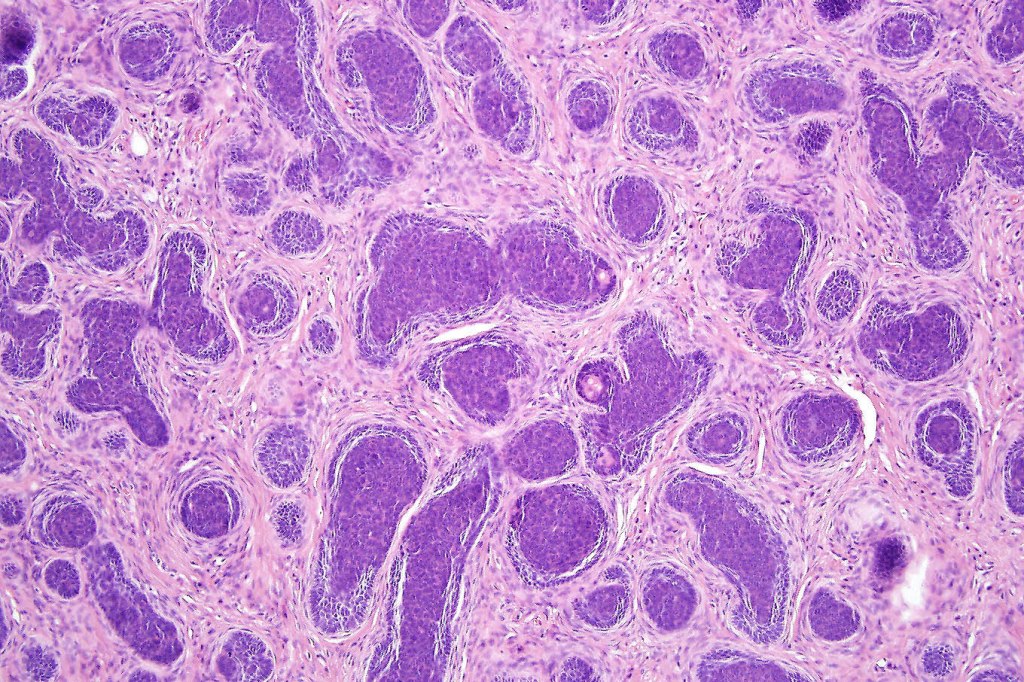

•Variable keratin cysts

•Clear cell change

•Sebaceous & glandular differentiation

•Cribriform and palisaded (rippled) pattern

•Pigmented variant

•Stromal component associated with indentation of epithelial component- follicular mesenchymal bodies (uncommon, more often seen in trichoepithelioma)

•Stromal amyloid often present